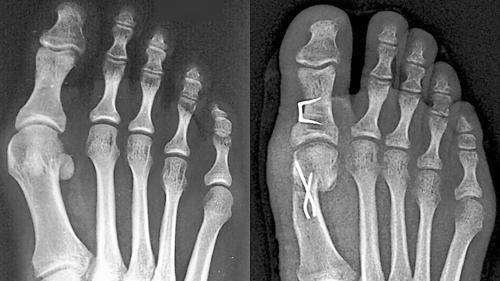

In den meisten Fällen werden Sehnen und Gelenkkapsel korrigiert, um die Fehlstellung des großen Zehs zu verringern. Der erste Mittelfußknochen und oft auch das Grundglied der Großzehe werden durchtrennt und so verschoben, dass der Zeh wieder geradesteht. Manchmal muss das erste Mittelfußgelenk auch versteift werden. Dabei kommen Metallplatten, Schrauben und Drähte zum Einsatz. In den ersten Wochen nach der Operation muss der Fuß stabil gehalten werden.